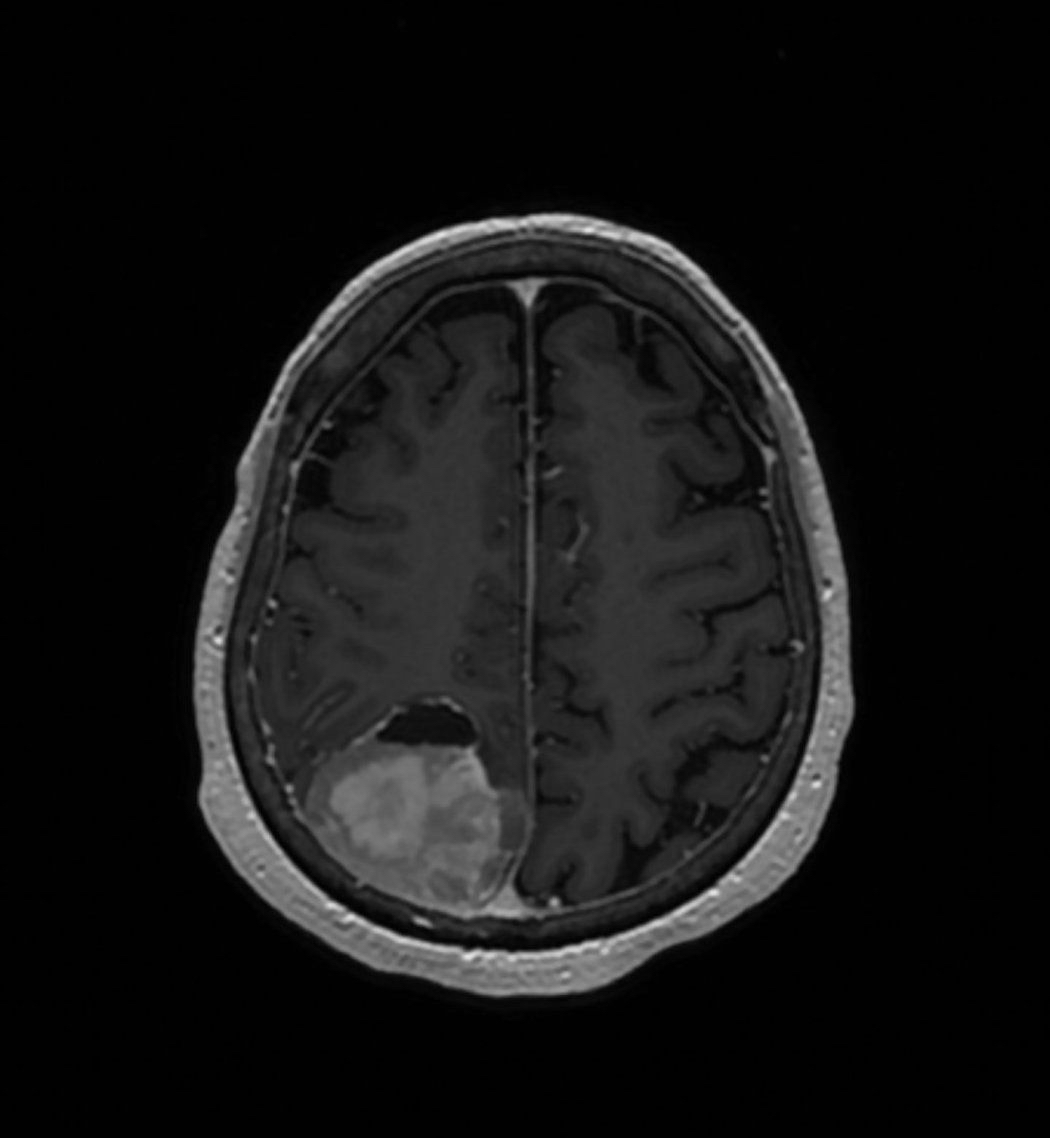

Write a Matlab code that applies the region growing algorithm to segment a

tumor in a medical image